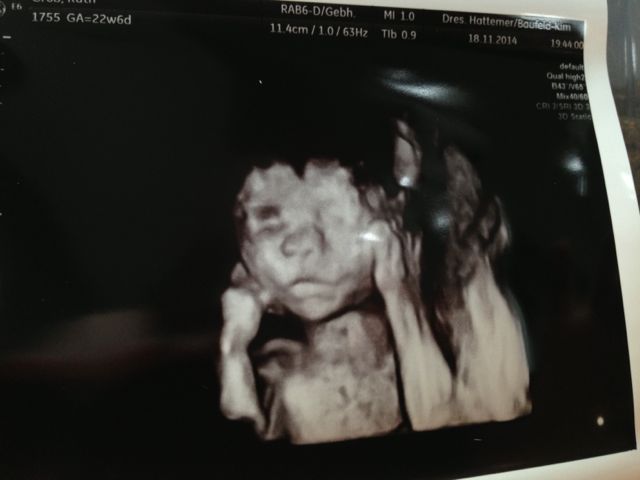

Ich hab fast Halbzeit, Wahnsinn, oder? Leider merke ich noch nichts von Krabbes Turnübungen, aber ich hoffe, dass das bald kommt. Dienstag hatten wir US mit Organbeurteilung und es ist alles bestens

Hier ist nach wie vor alles bestens. Der Bauch ist schon ziemlich gewachsen und die Krabbe turnt fleißig. Spüre sie sehr deutlich jetzt und auch der Papa kann sie von außen schon spüren. Er ist dann immer ganz ehrfürchtig

Die VU bei meiner FÄ war wieder toll. Die Krabbe hat beim US aber auch wieder alles gegeben und wieder einen ihrer Füße in der Mangel gehabt